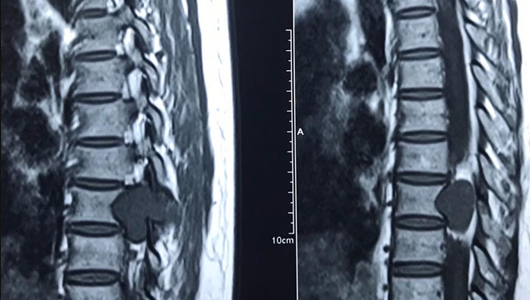

Trước hết, chúng ta cần biết được cấu trúc của đĩa đệm, từ đó mới hình dung được tình trạng phình xảy ra như thế nào tại cơ quan này. Vị trí của đĩa đệm là nằm giữa 2 đốt sống, cấu tạo gồm bao xơ và nhân nhầy. Đĩa đệm có chức năng làm giảm những áp lực, ma sát giữa 2 đốt sống với nhau mỗi khi chúng ta đi lại, hoạt động.

Phình đĩa đệm là tình trạng một vài vị trí trên bao xơ xuất hiện những tổn thương gây nên sự lỏng lẻo, đồng thời phần nhân nhầy bị chảy, rò rỉ ra khỏi phần trung tâm đĩa đệm nhưng chưa thoát ra hẳn phần bao xơ. Chính hiện tượng này đã khiến đĩa đệm bị phình lên, Phình ra và chèn ép các dây thần kinh xung quanh, từ đó tạo ra nhiều cơn đau ở phần đốt sống cho người bệnh.

Phình đĩa đệm L4 L5

L4 và L5 là vị trí xuất hiện tình trạng phình đĩa đệm phổ biến hơn cả. Đây là các đốt sống thấp nhất trong toàn bộ cột sống thắt lưng. Chúng phải chịu những áp lực lớn nhất khi có bất kỳ một tác động nào đè lên cột sống. Do đó, sẽ có nhiều tổn thương xảy ra ở 2 đốt sống L4 và L5 này hơn, trong số đó chính là phồng phồng đĩa đệm. Tuy nhiên, tình trạng phình đĩa đệm L4 và L5 vẫn có thể được coi là tình trạng phình nhẹ.